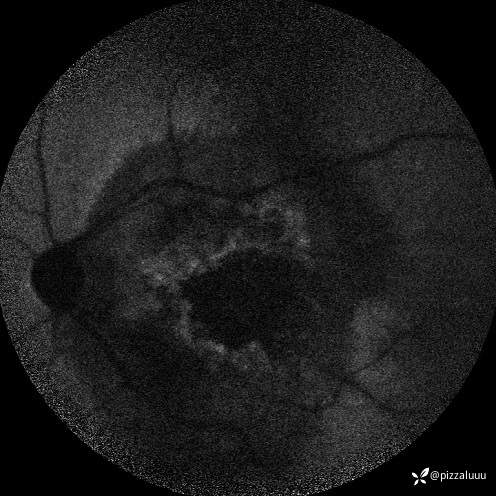

今天补充了FFA、AF和眼底照相。很典型的coats,后极部视网膜可见块状不规则而隆起的黄色渗出。AF可见病灶处低自发荧光。FFA所见:视网膜毛细血管扩张迂曲及异常血管形态,以小动脉明显,管壁呈囊样扩张,有梭形、串珠样动脉瘤。大片无灌注区。异常血管早期渗漏明显,形成强荧光斑,晚期荧光融合。由于大片黄白色渗出位于外丛状层,对视网膜血管荧光影响不大。可看到脉络膜背景荧光遮蔽。